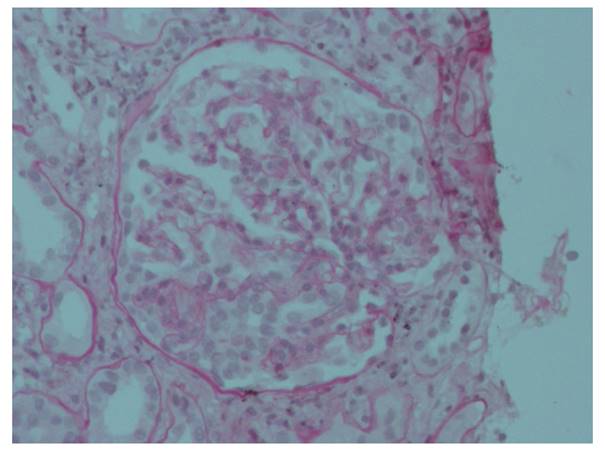

Se realizó biopsia renal cuyo informe fue: “GEFS, variante Colapsante, 17 glomérulos, ninguno globalmente esclerosado. Glomérulos aumentados de tamaño, expansión e hipercelularidad mesangial, rigidez segmentaria de asas capilares, dos con colapso capilar, hipertrofia e hiperplasia de podocitos. Túbulos con degeneración turbia y atrofia focal. Intersticio con LMN (1+) y fibrosis mínima. Inmunohistoquímica: Panqueratina (+), CD68 (+), Vimentina (-), en podocitos. Inmunofluorescencia: IgG (-), IgM (-), IgA (-), C3 (-), C1q (-), Kappa (-) y Lambda (-)”. (Figuras 1 y 2).

Figura 1 Tinción H/E 400X. Glomérulo aumentado de tamaño, con área de expansión e hipercelularidad mesangial leve, rigidez segmentaria y colapso capilar, hipertrofia e hiperplasia de podocitos.